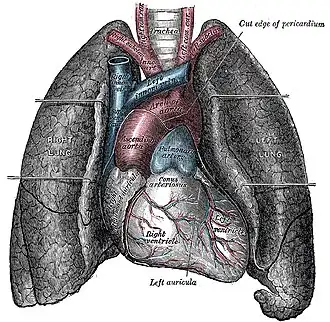

Кардиоло́гия (от др.-греч. καρδία — «сердце» и λόγος — «учение, наука») — обширный раздел медицины, занимающийся изучением сердечно-сосудистой системы человека: строения и развития сердца и сосудов, их функций, а также заболеваний, включая изучение причин их возникновения, механизмов развития, клинических проявлений, вопросов диагностики, а также разработку эффективных методов их лечения и профилактики. Кроме того, в сфере ведения кардиологии лежат проблемы медицинской реабилитации лиц с поражениями сердечно-сосудистой системы, которые занимают второе место по смерти человека. На другом полюсе от кардиологии в плане дифференциальной диагностики и лечения сердечно-сосудистых болезней очень часто находятся такие хирургические дисциплины, как: сосудистая, сердечно-сосудистая хирургия, торакальная хирургия, флебология, абдоминальная хирургия и нейрохирургия. Как и многие другие терапевтические дисциплины медицины - кардиология также часто тесно системно и топографически связана с гематологией и тесно сотрудничает по наиболее частым этио-патогеническим вратам болезней сердца с: генетикой, инфектологией, токсикологией, ревматологией, эндокринологией и Нефрологией, а также с пульмонологией

Кардиология изучает такие патологические состояния, как ишемическая болезнь сердца (ИБС), гипертоническая болезнь, врождённые пороки сердца, приобретённые пороки сердца, цереброваскулярные заболевания и другие. Сегодня доля кардиологической патологии в структуре смертности населения развитых стран составляет 40—60 %, при этом продолжающийся рост заболеваемости и поражение людей всё более молодого возраста, что делает сердечно-сосудистые заболевания важнейшей медико-социальной проблемой здравоохранения.

Кардиология занимается изучением, диагностикой, лечением и профилактикой следующих заболеваний:

- пороки сердца (врождённые и приобретённые);